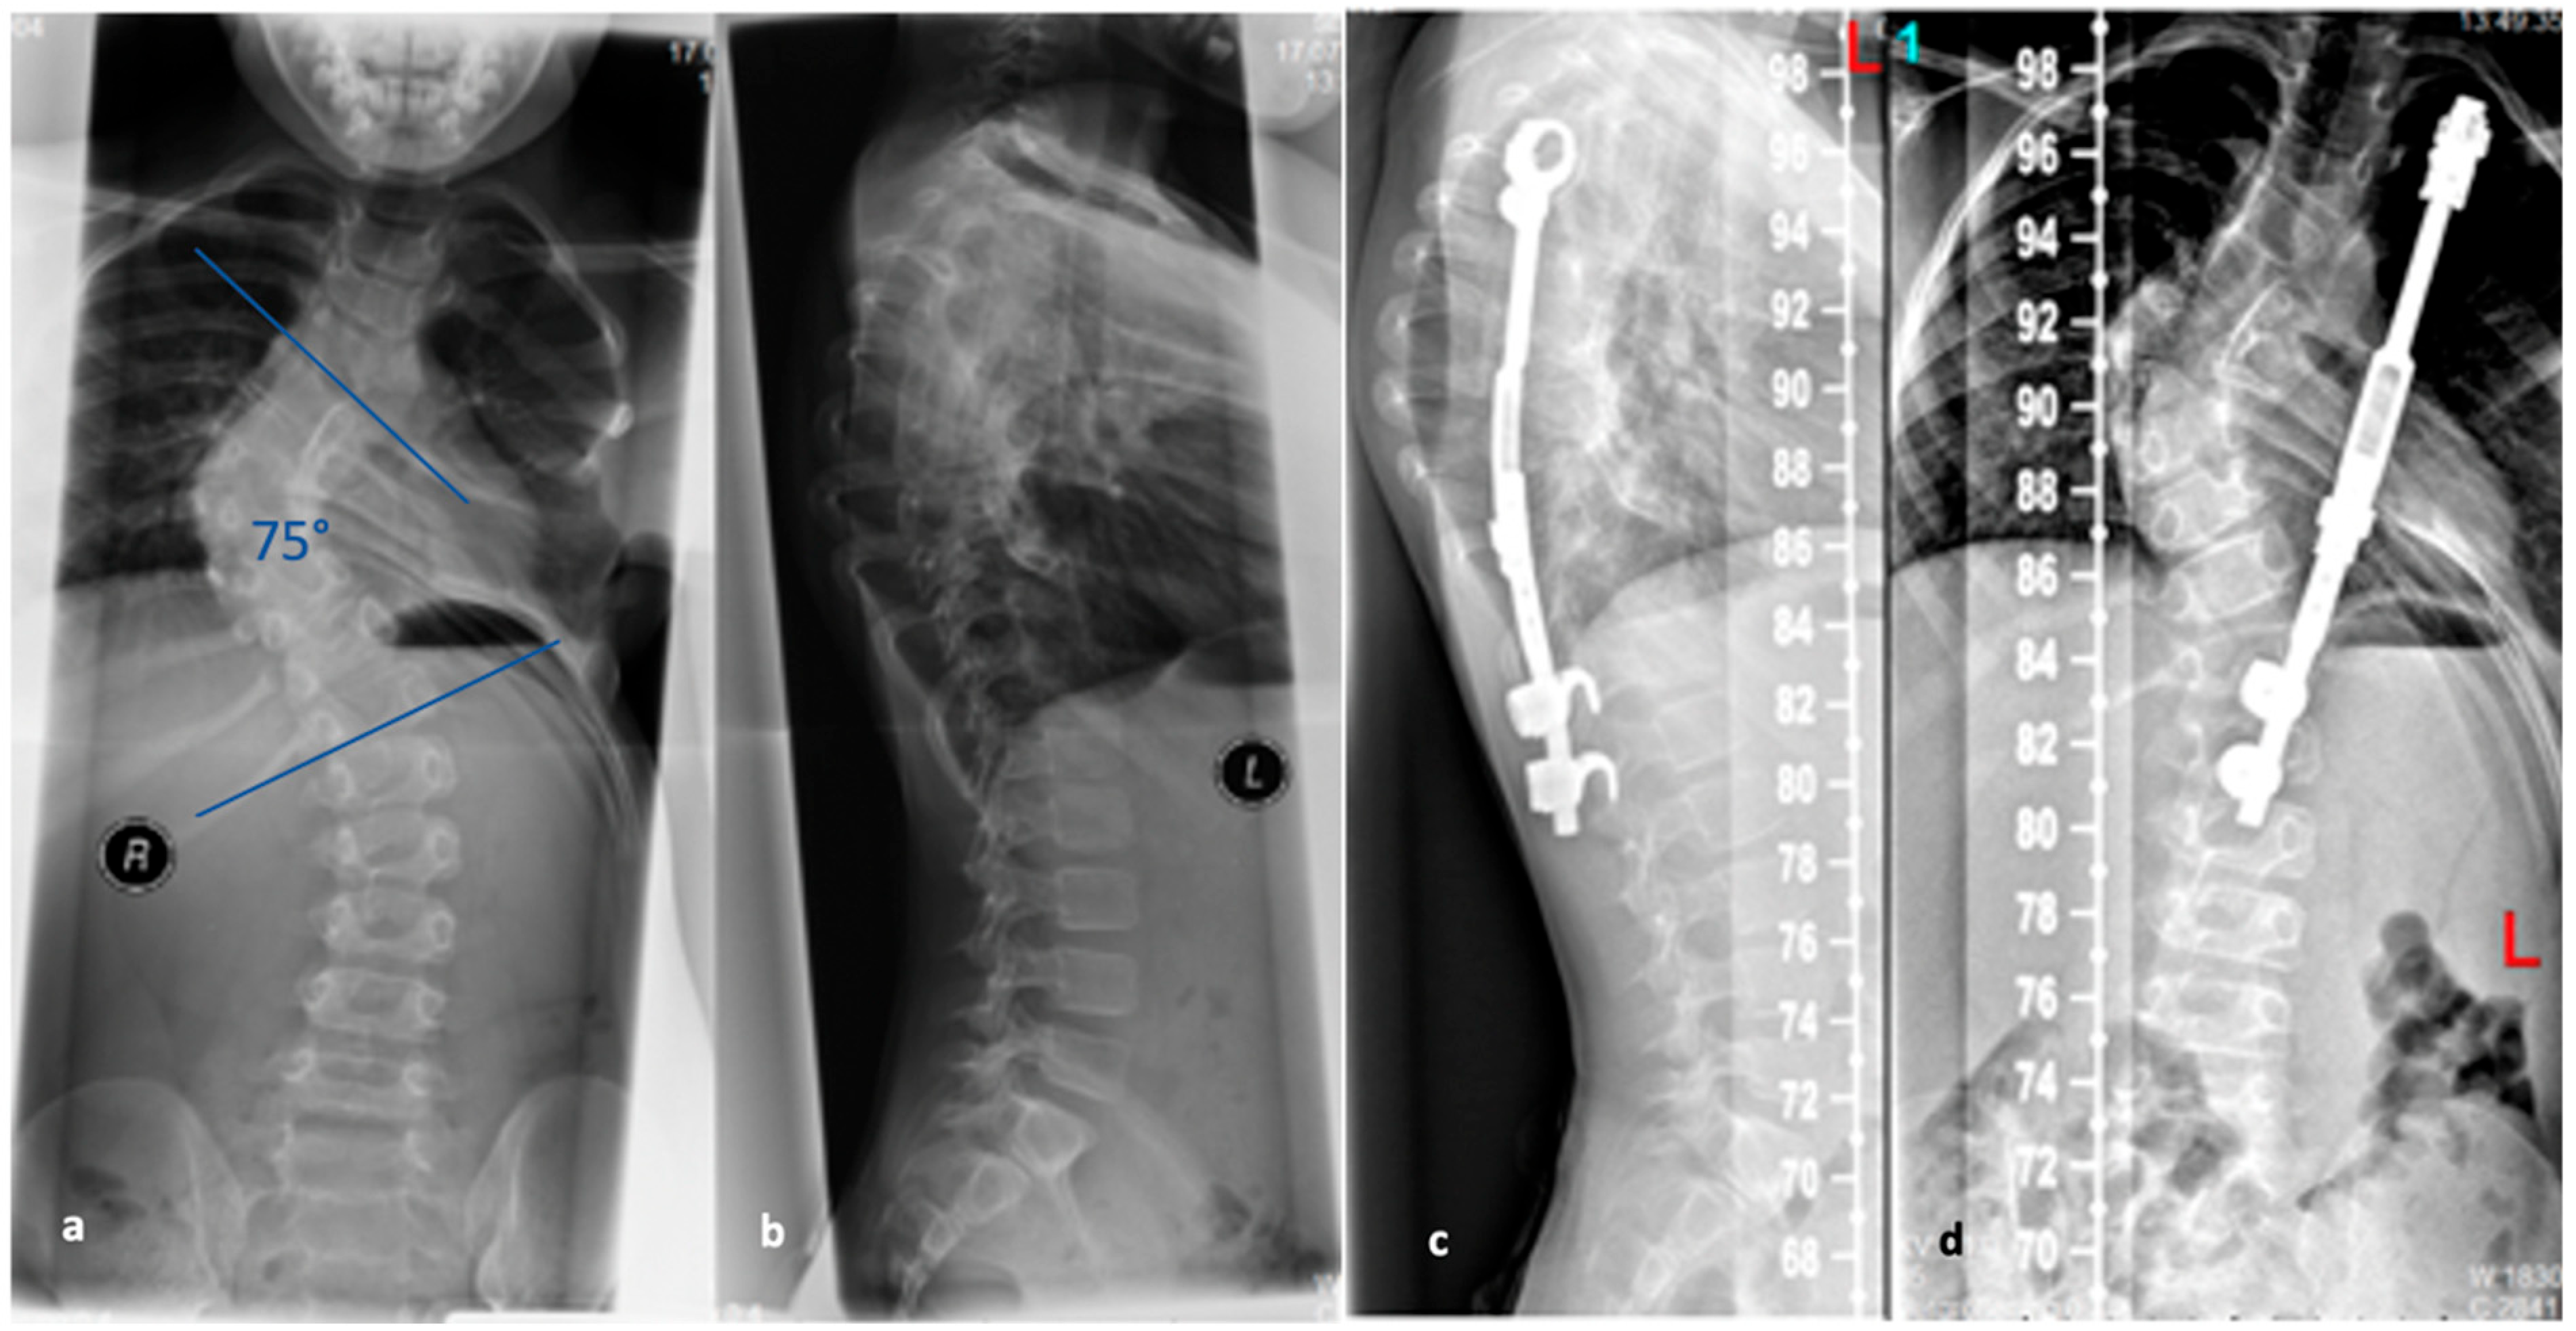

Figure 4. (a,b). Preoperative representation of the scoliosis and (c,d). Postoperative image following expansion thoracoplasty and implantation of the vertical expandable prosthetic titanium rib (VEPTR), attached proximal to the rib and distal to the laminae (reprinted with permission [10]).

The VEPTR system is a special type of scoliosis correction, and it is not considered as a classic growing rod. Originally, the system was used in children with congenital and highly progressive spinal deformities including unilateral brace formation and rib deformities with impending thoracic insufficiency syndrome [44]. The average age of 3.3 years at the time of surgery is lower for the VEPTR procedure in contrast to the TGR procedures. Currently, the main indication is thoracic scoliosis in congenital scoliosis with rib fusion, unilateral unsegmented braces, and contralateral hemivertebrae. This deformity is associated with severe thoracic asymmetry and markedly limited vital capacity of the lungs. The advantage of expansion thoracoplasty is that secondary correction of the spine can be achieved via correction of the rib deformity by rib osteotomies and VEPTR implantation without using a second approach in this area and thus increasing the risk for spontaneous fusions [45]. The VEPTR is a longitudinal, extendable titanium implant that is anchored to each of the caudal and cranial ribs using hooks of the concave hemithorax; see Figure 4. This “titanium rib” is also surgically expanded approximately every six months until growth is complete. Components may have to be replaced when the distraction distance is depleted. The main complication is cut-out or dislocation of the fixation to the ribs. By modifying the implant design, the complication rate could be reduced. In addition to intercostal connections from rib to rib, the VEPTR also offers the possibility of fixation to the laminae of the vertebral bodies or support on the pelvis.